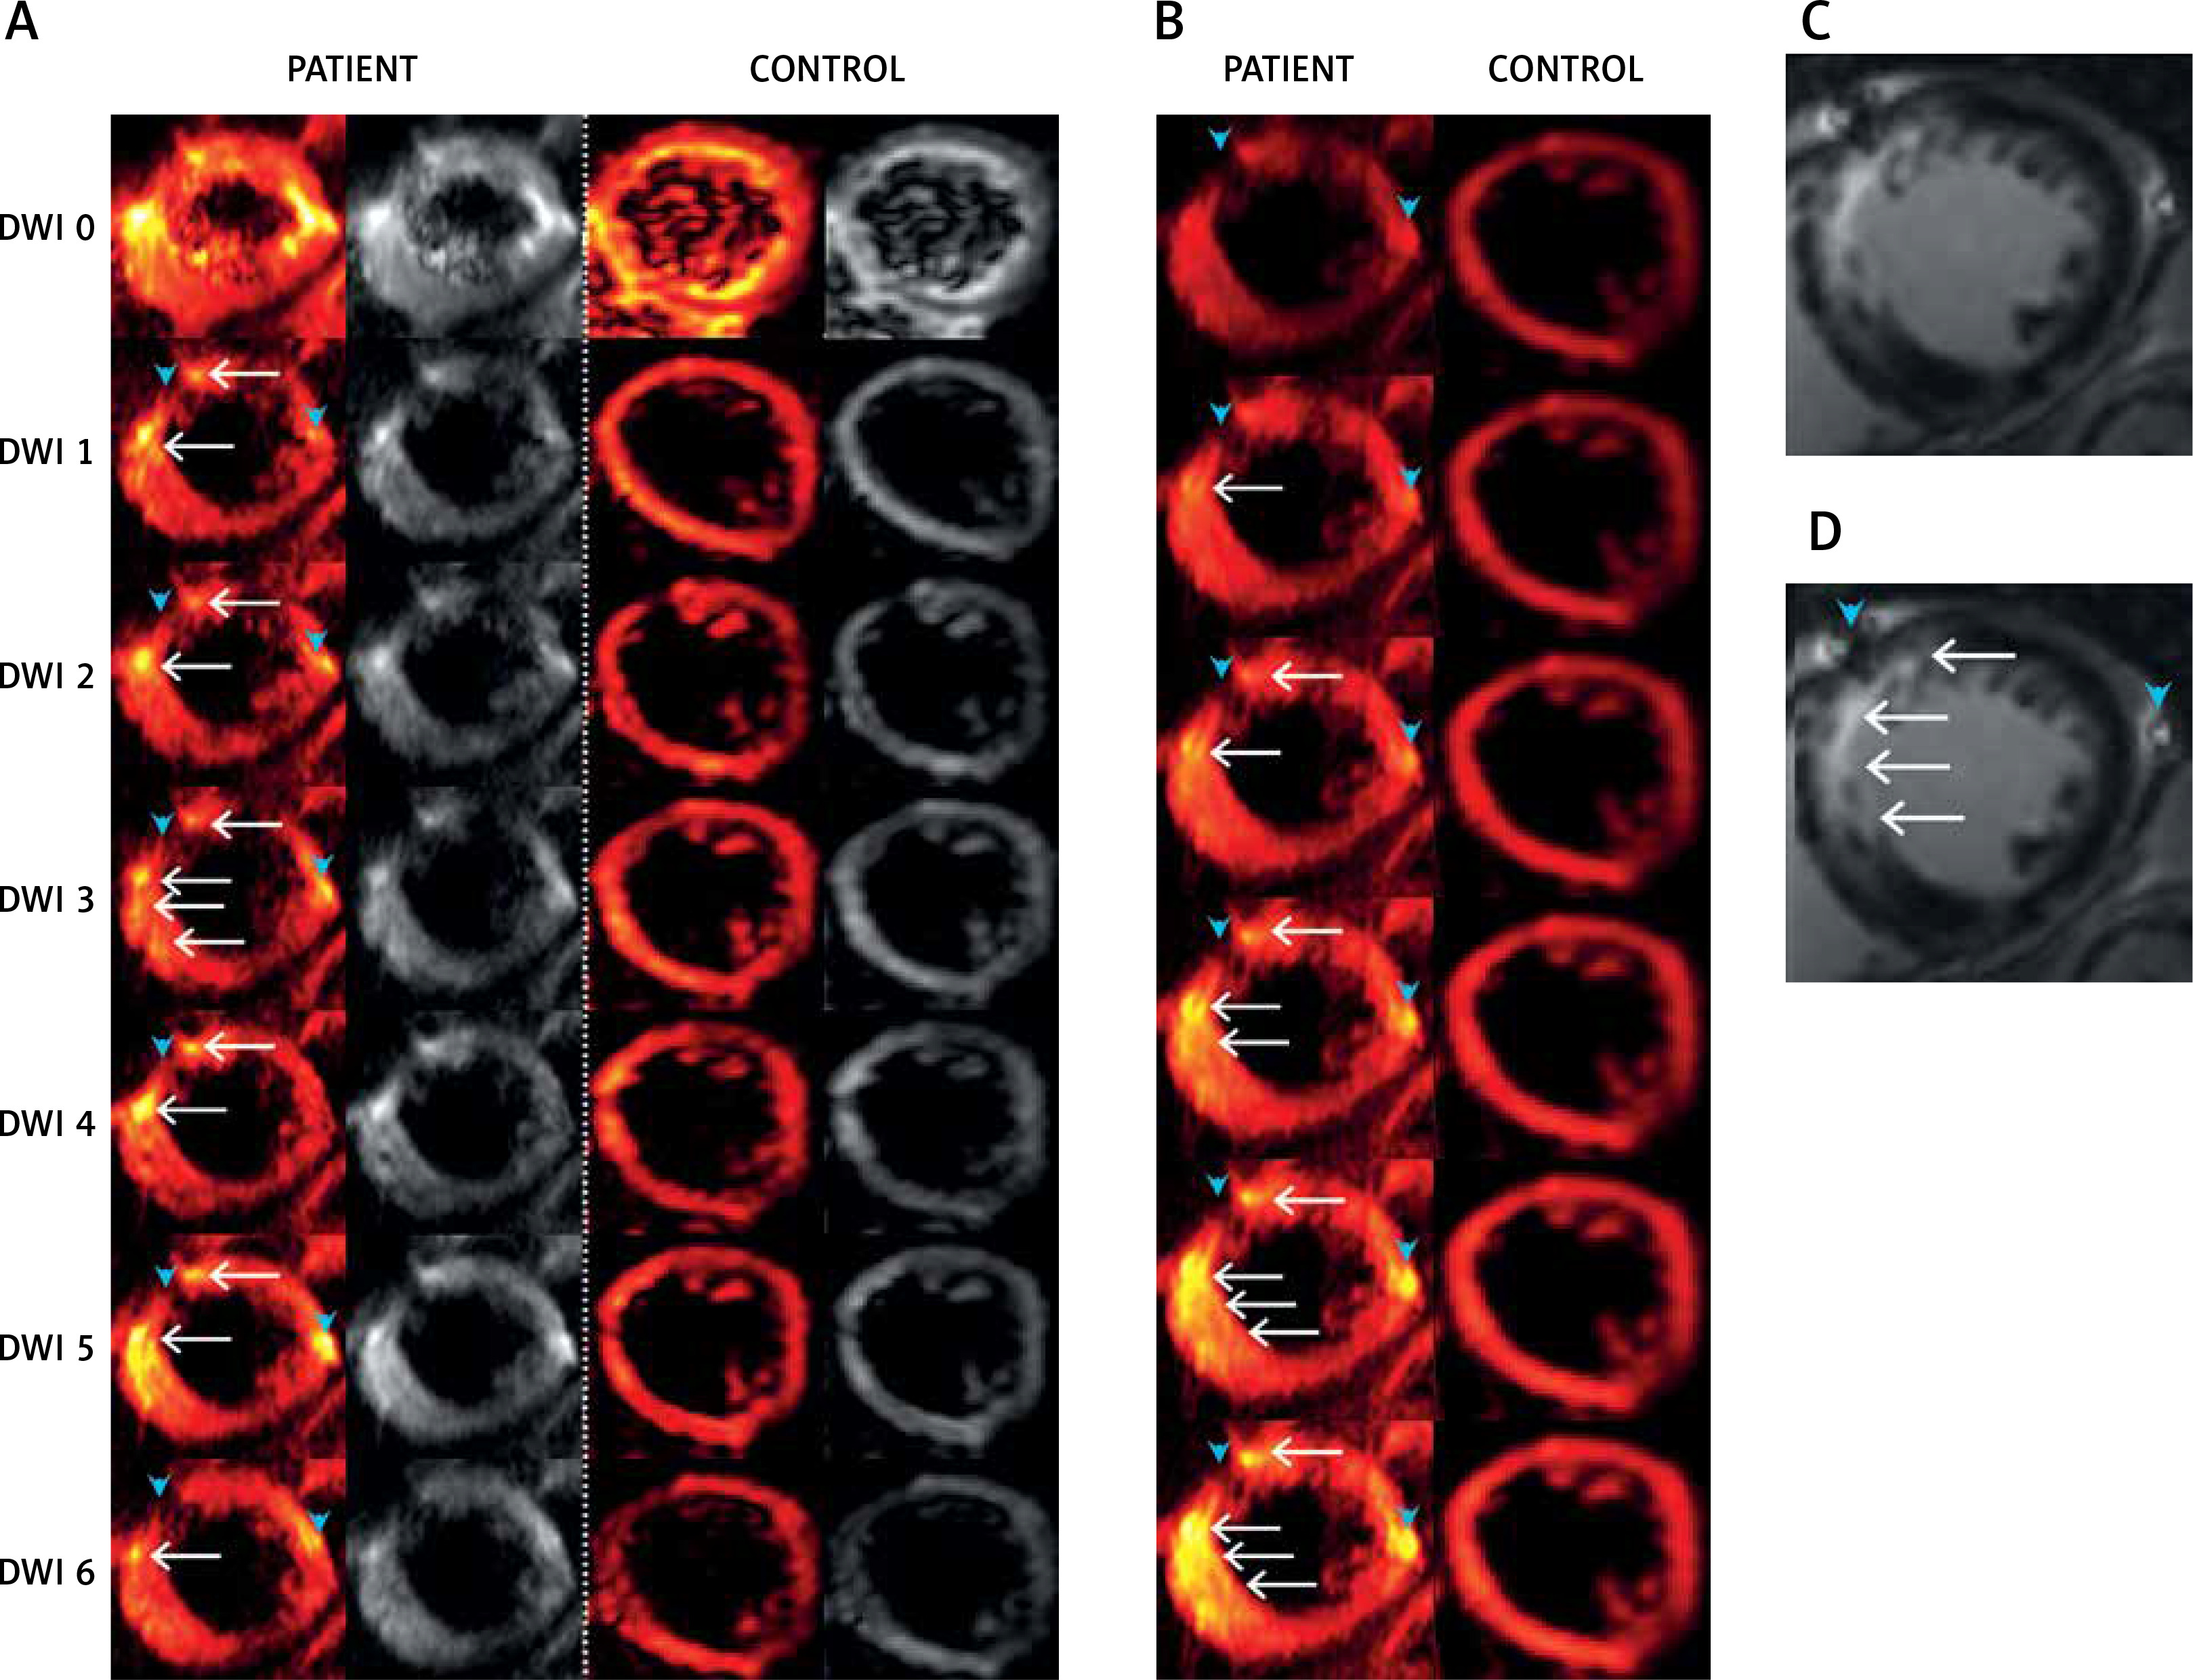

Figure 1

Typical examples of diffusion-weighted images of the human heart in vivo using the methodology we have developed. Images are from a patient (PATIENT) with acute anterior myocardial infarction (day 6 after pPCI) and from a healthy control (CONTROL). A – Raw multi-directional DWI images used for diffusion tensor calculation; B – use of an increased image contrast to enhance visualization of the hyperintense spots (infarct area according to classic gadolinium imaging). In (A) and (B) from top to bottom – diffusion-weighted images for b = 0 s×mm–2 (DWI 0) and six DWIs (DWI 1-6; from top to bottom) obtained for different non-collinear directions (hot color scale, left side, and gray scale, right side of each panel) (A). Images obtained using an increasing gradient of auto-contrasting (from top to bottom) (B). Typical T1-weighted images with late gadolinium enhancement of the same patient heart (infarct areas indicated by white arrows; reference images). C, D – White arrows indicate infarct areas, blue arrowheads indicate vascular scaffold and fatty signal, while white arrowheads indicate microvascular obstruction zone. Note: (i) feasibility to obtain the human heart DWI images using the algorithm that we have developed, and (ii) increased DWI signal intensity in the infarcted areas, particularly visible on image contrast enhancement (B), allowing one to achieve improved visualization that is independent of the DWI direction and may be useful clinically, particularly as subtle damage areas are identified that are only in part amenable to conventional gadolinium contrast-based cardiac MRI imaging (see text for details)

Our application of an SE-EPI sequence with cardiac gating allowed registration of a reasonable signal coming from the heart muscle (Figure 1). With our algorithm, this was achieved despite the reduced number of scans, lower b-value and increased resolution with lower attainable TE in comparison to the previous attempts [2, 10–17]. Considerably shorter TE in cardiac DTI can be indeed found in the literature, but for the stimulated-echo (STE) based sequences, which enable dMRI with the same b-value, but lower SNR [18]. However, due to lower SNR, STE is usually applied with multiple scans. This, for a moving object like the heart, can lead to erroneous averaging. MD and different tensor metrics can also be more accurately determined by using SE sequences [16]. We hypothesize, similarly to Mekkaoui et al. [2], that in the near future a major move from STE to SE-based imaging will occur in cardiac DTI. This move is anticipated to be facilitated by the increasing availability of clinical scanning at higher magnetic field gradients [2].

Our work indicates that the A1 and A2 segments may be highly discernible on DW images obtained according to our algorithm. This is particularly relevant for the myocardial infarction zone in these segments (note DWI signal hyperintensity in Figure 1 A, DWI 1-6, white arrows). No hyperintense spots were visible for the healthy control.

There were some important features in the DWI images, interesting for dMRI of AMI patients. Patient had an implanted stent (Figures 1 A, B, D, blue arrowhead on the left), which in DWI images is visible as a diffusion signal loss. Moreover, adjacent fatty accumulation (Figures 2, B, D blue arrowhead on the right) caused an effect similar to the infarction. Therefore, referential MRI (e.g. T1 , T2 ) or additional clinical data are required for a proper interpretation of dMRI. Multi-shot SE-EPI with our algorithm enabled the application of a high resolution, which greatly helped to capture the details of the infarction areas – strong hyperintense spot, uniform across the myocardial wall. As shown by Mazur et al. [1], using the same algorithm for the patient shortly after the myocardial infarction incident it was also possible to distinguish a hypointense area reflecting microvascular obstruction between hyperintense strand-like areas associated with infarction [1]. This shows that with a carefully chosen SE-EPI DTI sequence protocol, details of the damaged zones can be almost as visible as in LGE images (Figures 1 C, D).

Figure 1 B shows the method for distinguishing damaged myocardial zones. We propose to average all DWIs (from Figure 1 A), rescale all subjects to the same intensity range to enable inter-patient comparison and then increase the contrast by changing the display range. In this way, consecutive display shows more hyperintense spots, while the most severe damage appears first and the most benign last (Figure 2 B from top to bottom images). This is an important area for further research as DWI of the heart might depict areas with subtle damage that may be particularly amenable to myocardial reparation and regeneration using cell-based and other agents [10, 19]. In contrast, the post-infarction scar (classically viewed as “irreversible” injury that may be less amenable to cellular reparation in absence of simultaneous scaffold use [19, 20]) might be better distinguished using typical contrast-enhanced MRI imaging (cf., Figure 1 B). Our findings are consistent with the concept that cardiac DWI might make it possible to reveal (and potentially quantify) less severely damaged regions of the heart and that this imaging modality might play an important role in monitoring the effect of therapies aimed at myocardial reparation and regeneration [4, 20, 21].